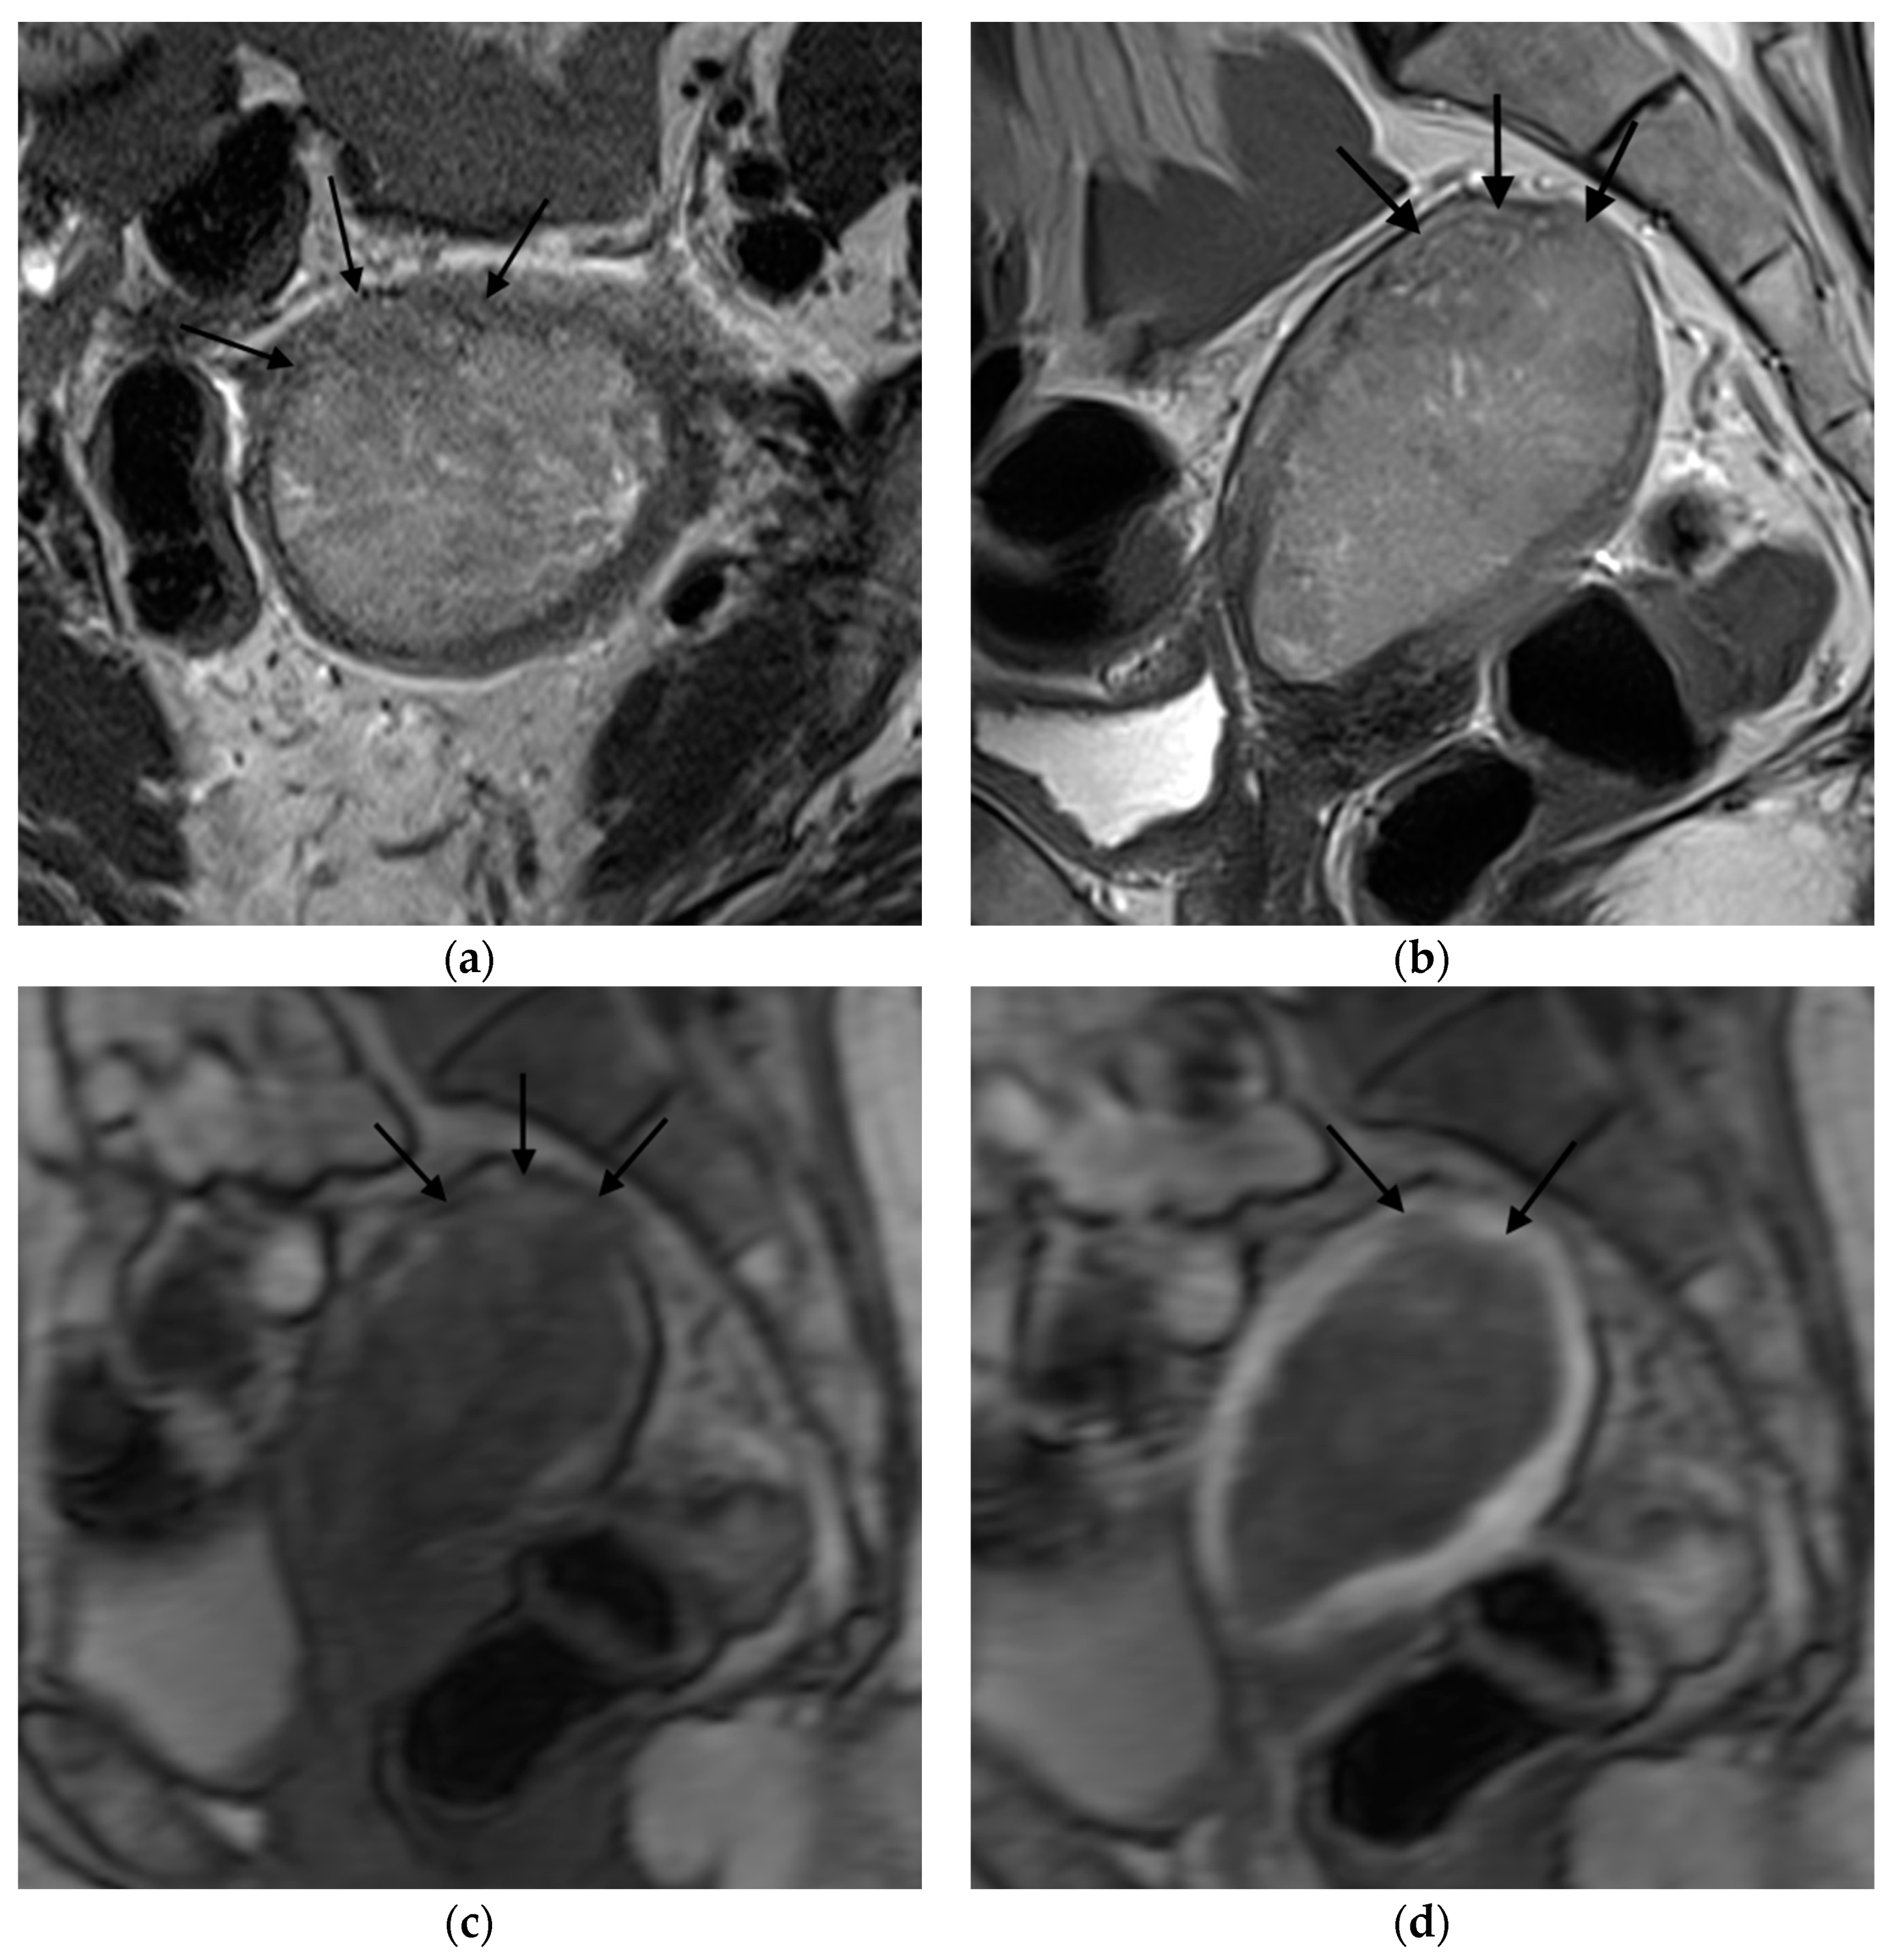

Figure 1, Figure 2, Figure 3 and Figure 4 depict the representative MRI images of tumors with < 50% myometrial invasion and ≥50% myometrial invasion, as well as the representative combined T2WI+DCE-MRI images for false-positive and false-negative cases, respectively. The diagnostic performance of MRI in predicting the depth of myometrial invasion is presented in Table 2 and Table 3. The depth of myometrial invasion (any depth) was correctly determined in 75% (n = 24) and 78% (n = 25) of cases on T2WI and DCE-MRI alone, respectively, whereas the percentage increased to 91% (n = 29) of cases when the T2W images were read together with those obtained by DCE-MRI.

Figure 2. Representative MRI images of endometrial carcinoma with ≥50% myometrial invasion. (a) Axial T2WI, (b) sagittal T2WI, and (c,d) sagittal DCE-MRI images during the early (c) and late (d) acquisition stages. Tumors (arrow) with ≥50% myometrial invasion presented as iso- to mildly hyperintense on T2WI compared to the myometrium (a,b) with disruption of the junctional zone. On DCE-MRI, the tumors appeared as hypointense masses compared to the adjacent myometrium with interrupted subendometrial enhancement (SEE) (c), irregular tumor-to-myometrium interface, and extension of the tumor beyond the outer half of the myometrium (d). Abbreviations: MRI, magnetic resonance imaging; dynamic contrast-enhanced magnetic resonance imaging (DCE-MRI); T2WI, T2-weighted imaging; subendometrial enhancement (SEE).